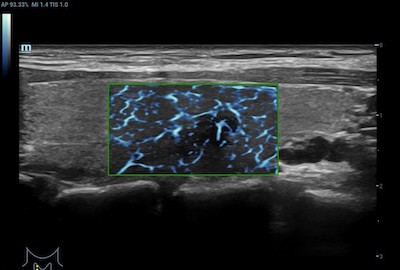

- Musculoskeletal – CDI may be used to visualize rheumatological changes in diseased joints and can provide diagnostic information for assessing damage to tendons and ligaments.

Color Doppler Imaging of Musculoskeletal Lesion